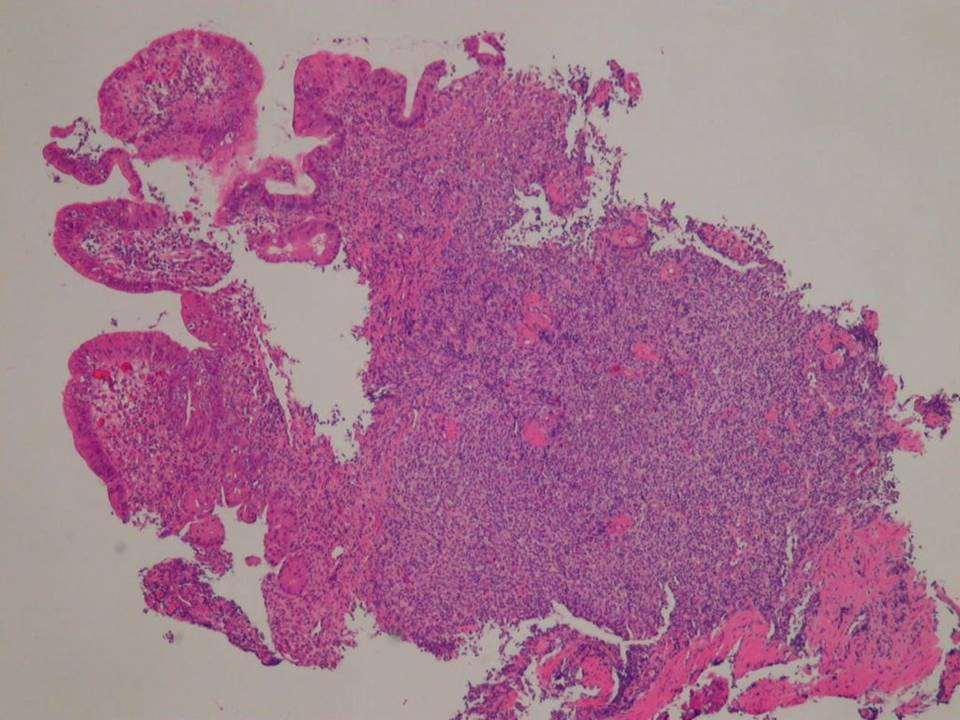

• 4. A 54 year old woman with multiple antral erosions: The biopsy shows a dense and diffuse lymphoid infiltrate in the lamina propria with infiltration of the glands by several aggregates of lymphocytes (lymphoepithelial lesions).

•.J Answer

• MALT lymphoma: Causes

Morphology (Centrocyte-like cells, LEL’s, plasma cell differentiation, Follicular colonisation)

Immunohistochemistry

• Other gastric lymphomas (DLBCL, mantle cell – multiple polyposis)